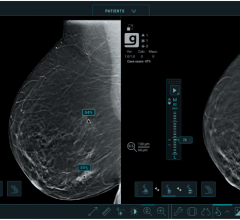

December 7, 2020 — Breast cancer screening with digital breast tomosynthesis (DBT) offers significant advantages over ...

November 11, 2020 — Digital breast tomosynthesis (DBT), in combination with synthetic mammography, improves cancer ...